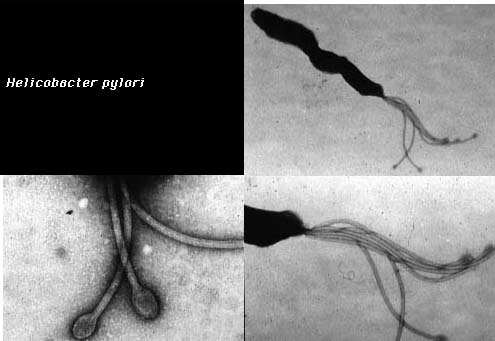

Helicobacter is a curved (vibrioid) Gram-negative bacterium which has been implicated in causing peptic ulcer disease (H. pylori). Helicobacter survives in the stomach by secreting urease, which makes the environment more alkaline. H. pylori also has flagella with thickened ends (see photo) to enable it to move through the thick gastric mucosa.